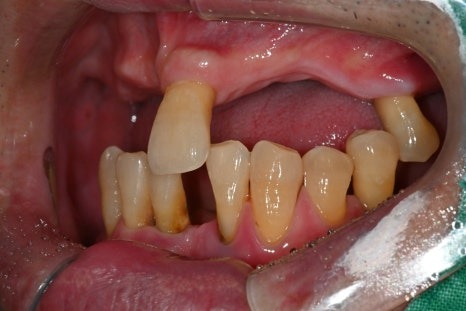

· 상악은 잇몸뼈가 매우 얇고 치아가 거의 남아 있지 않은 상태

· 하악은 부분 결손과 앞니의 심한 동요

· 식사가 어려울 정도로 기능 저하가 심한 상태